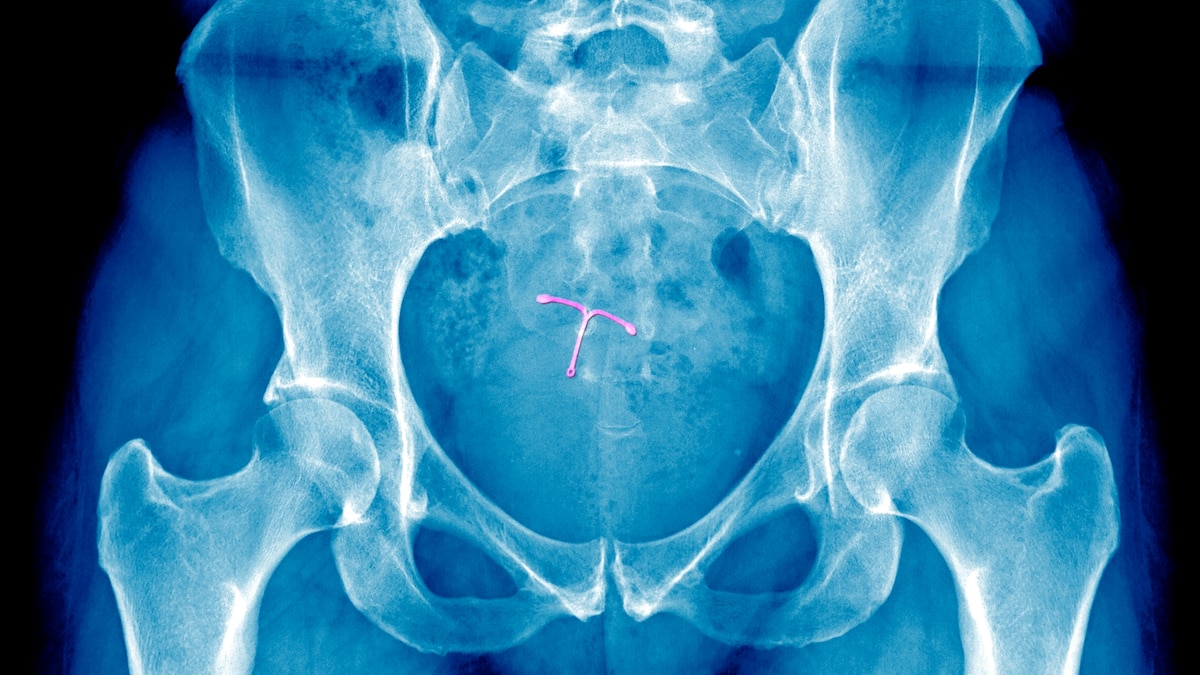

The complexity of pain management is further exacerbated by research that has produced mixed results regarding various strategies. Real-world scenarios often yield unpredictable outcomes. For instance, King reflects on her experience, stating, “When I had an IUD placed with a cervical block, it didn’t help at all. It was exceedingly painful.”